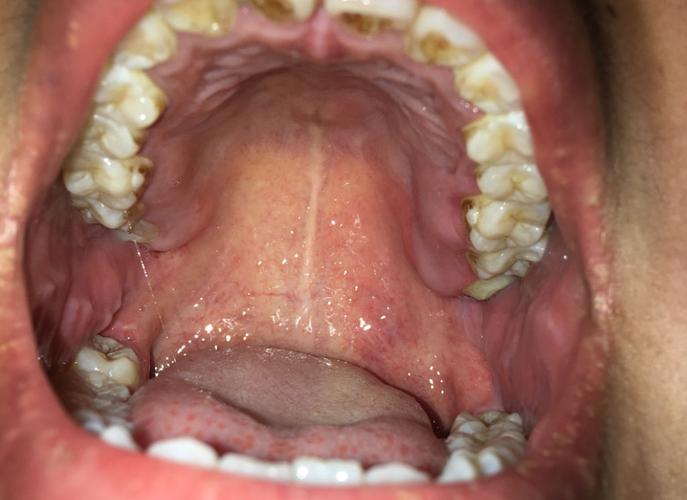

婴儿口腔上颚发黄照片

婴儿口腔上颚发黄的常见原因

婴儿口腔上颚发黄,绝大多数情况是良性的,但也可能是某些疾病的信号,以下是几种可能性,从最常见到较少见排列:

上皮珠/马牙 (Epstein's Pearls / Bohn's Nodules)

这是正常的生理现象,不是疾病。

- 外观: 在上颚中线附近,可以看到一些白色或黄白色、米粒大小或稍大的小颗粒或小泡。

- 质地: 它们是坚韧的、角质化的,像小石头一样,不会移动,也不会被擦掉。

- 伴随症状: 完全无症状,宝宝不会感到疼痛,对吃奶没有影响,它们通常在几周或几个月内自行脱落。